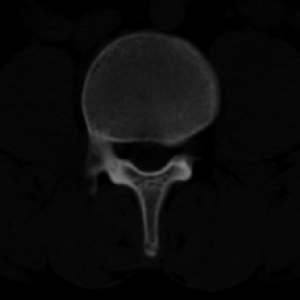

男,20,士兵,腰痛3年多,无外伤史

都是同一幅图啊,椎体内椎间盘突出。

考虑:1、多发许莫尔氏结节形成;

2、建议平行腰5椎体扫描或冠矢状曲面重建除外椎弓峡部断裂。

1、多发许莫尔氏结节形成;

2、椎弓峡部断裂。

3、l5轻度滑脱。

1、多发许莫氏结节。

2、腰5双侧椎弓峡部崩裂并i度前滑脱,楼主椎间盘扫描角度有问题,另外需要反倾角扫描腰5椎弓峡部。

2、腰5双侧椎弓峡部崩裂并i度前滑脱。